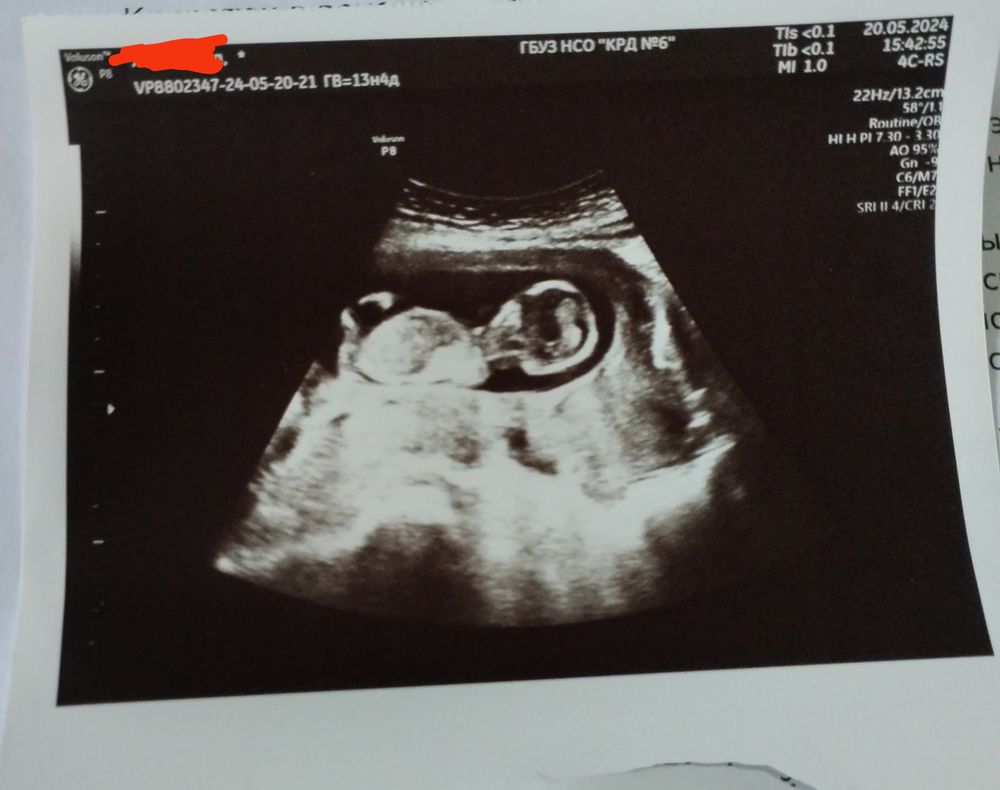

Добрый вечер всем у нас уже вечер вот и как все мы тоже пытались почти год у нас получилось ))))))) пошла первый скрининг результат на руках и еще фото тоже распечатали сейчас конечно не видно но как вы думайте кто у нас будет ?? Кровь сдала ждём результат все таки не терпится 🫣

Это гадание на кофейной гуще) нам на 12 неделе сказали, что девочка, узист хорошая и на хорошем аппарате, смотрела долго. По нипт - мальчик) так что ждите лучше кровь))